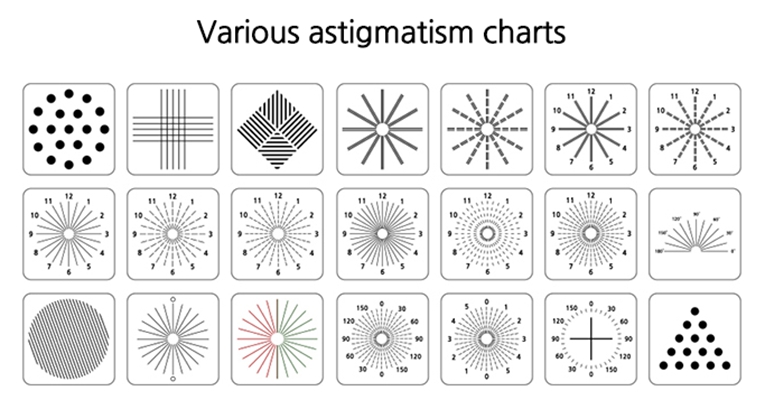

散光圖片

散光度數測試圖 (48)

散光度數測試圖 (49)

散光度數測試圖 (5)

散光度數測試圖 (50)

散光度數測試圖 (51)

散光度數測試圖 (6)

散光度數測試圖 (7)

散光度數測試圖 (8)

散光度數測試圖 (9)

散光度數測試圖 (39)

散光度數測試圖 (4)

散光度數測試圖 (40)

散光度數測試圖 (41)

散光度數測試圖 (42)

散光度數測試圖 (44)

散光度數測試圖 (45)

散光度數測試圖 (46)

散光度數測試圖 (47)

散光度數測試圖 (35)